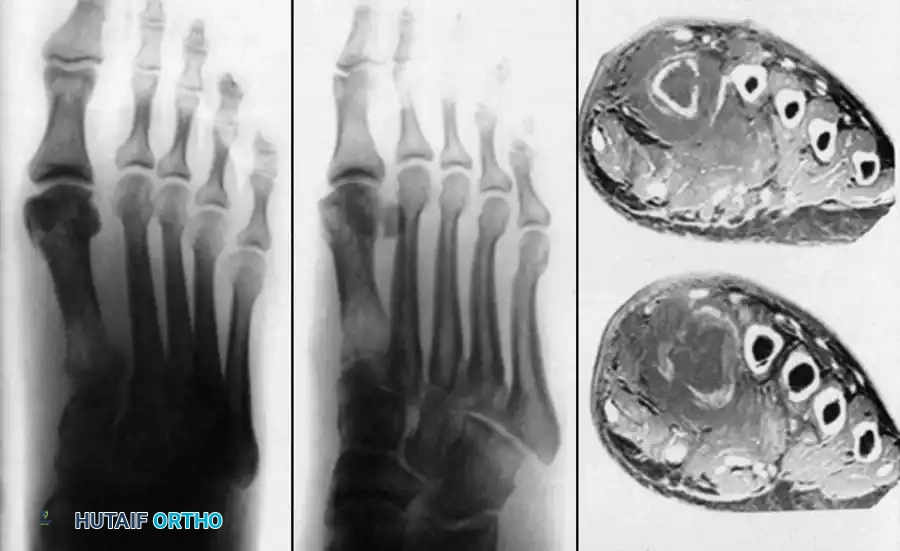

The Foot and Ankle

Tuberculosis of the foot and ankle often presents with midfoot swelling, sinus tract formation, and severe pain upon weight-bearing. The calcaneus and talus are frequently involved, presenting with cystic, lytic lesions that can compromise the structural integrity of the hindfoot.

Advanced imaging, as seen above, often reveals extensive midfoot destruction and soft-tissue abscess formation. Surgical management in the early stages involves aggressive tenosynovectomy and curettage of lytic lesions. Bone grafting may be required to fill cavitary defects in the calcaneus.

In advanced cases with articular collapse, arthrodesis is the treatment of choice. For midfoot and hindfoot involvement, a triple arthrodesis or tailored midfoot fusion is performed to restore a plantigrade, stable foot.